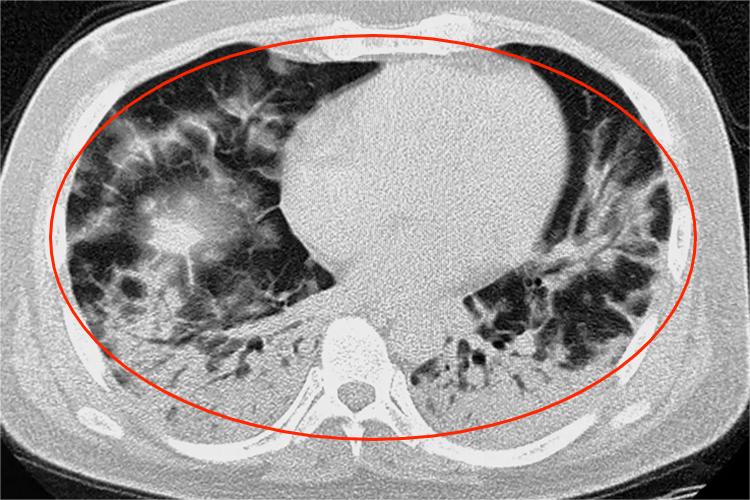

3、较重症状:症状较为严重的患者,发热可能持续且体温较高,超过39℃。咳嗽频繁且剧烈,出现大量咳痰,甚至有血丝。呼吸困难逐渐加重,活动后气促明显,还可能伴有胸痛、心悸等症状。

4、严重症状:重症患者会出现严重的呼吸困难,呼吸急促、窘迫,需要依靠吸氧或呼吸机辅助呼吸。可能出现多器官功能障碍,如急性呼吸窘迫综合征、急性肾损伤、心力衰竭等,还可能有休克的表现。